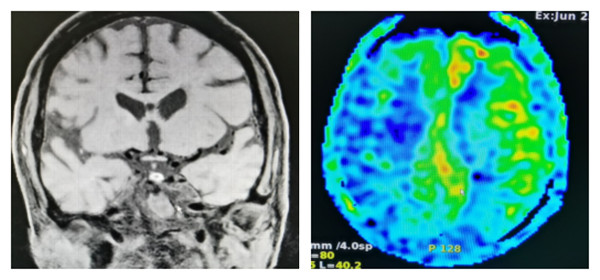

患者刘某,69岁,2周前出现左侧肢体无力,外院DSA提示右侧大脑中动脉闭塞,给予内科保守治疗后效果不佳,肢体无力仍进行性加重。患者及家属抱着急切的心情就诊于我院神经内科。接诊医生巩雨查看患者发现左侧肢体完全不能移动,复查头颅CT显示右侧大脑半球分水岭梗死。影像科脑动脉高分辨MRI及灌注成像显示右侧大脑中动脉闭塞段长度约10mm,右侧大脑半球灌注严重不足。全科讨论后认为该患者右侧大脑中动脉闭塞导致的低灌注是病情进行性加重的主要病因;脑动脉高分辨MRI及外院DSA显示右侧大脑中动脉闭塞段不是特别长,远端血管床存在。综合考虑,开通闭塞的大脑中动脉是可能的和必要的,但是手术难度及风险较大。向患者及家属详谈手术必要性及风险后家属和患者均强烈要求手术治疗。神经介入团队基于患者情况充分术前准备,制定详细方案,最终在麻醉科配合下由张桂莲主任医师和王虎清副主任医师进行右侧大脑中动脉闭塞再通术。在张磊主治医师医师、汤有飞进修医师和神经内科护理团队的精心照料下恢复良好,术后第二天患者左下肢就能抬离床面。目前患者已转入我院康复科进一步治疗。

术前脑动脉高分辨MRI和灌注MRI